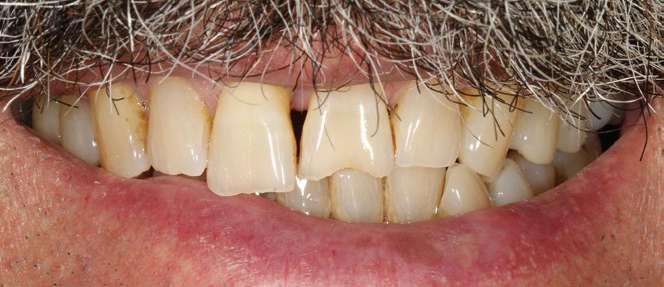

Cinco años después, llevamos a cabo un nuevo cone-beam y en el podemos observar la evolución del implante y de la sobre-corrección vestibular llevada a cabo en la cirugía inicial. Tanto el implante como el hueso que se ha formado a nivel vestibular fruto del injerto empleado está estable y se mantiene sin pérdida ósea asociada, tal como mostramos en los cortes del cone-beam

inicial y final a los 5 años de seguimiento (figura 19). En las imágenes intraorales tomadas en este punto del seguimiento se constata el éxito del tratamiento (figuras 20 y 21). En la radiografía periapical, observamos con mayor detalle la regeneración del tejido óseo del diente en posición 11 así como la estabilidad ósea del implante (figuras 22 y 23).

Figura 19. Imagen inicial del cone-beam y final con el implante cargado a los 5 años de seguimiento con la estabilidad del implante y del hueso generado mediante el injerto

Figuras 20 y 21. Imagen inicial y final de paciente tras 5 años de seguimiento. En ellas observamos la estabilidad del tratamiento logrado con el implante.